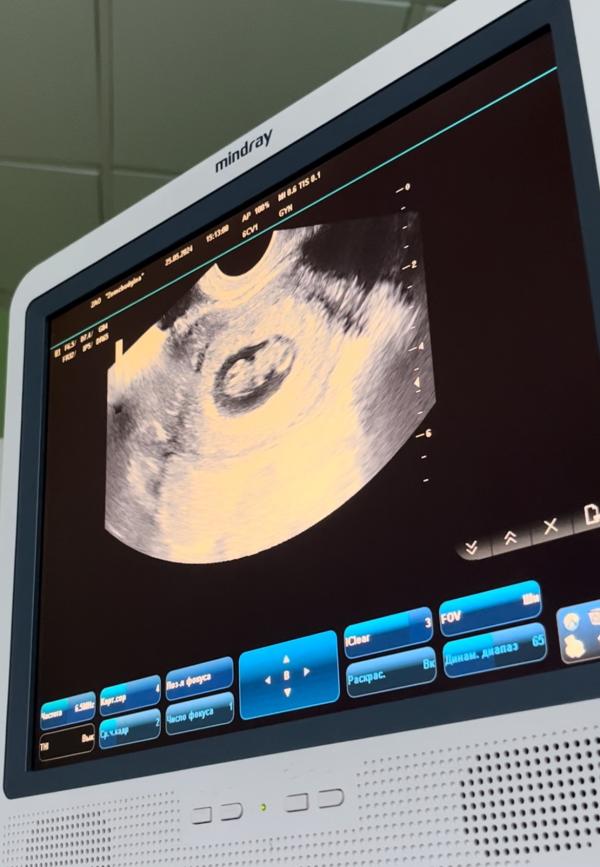

Креветочка перестала быть креветочкой 😂

8.4 по месячным

Ктр 23 на 9 недель

Сердцебиение почему то не мерили, но слушали, и то ладно)

Скрининг уже через 3 недельки ☺️